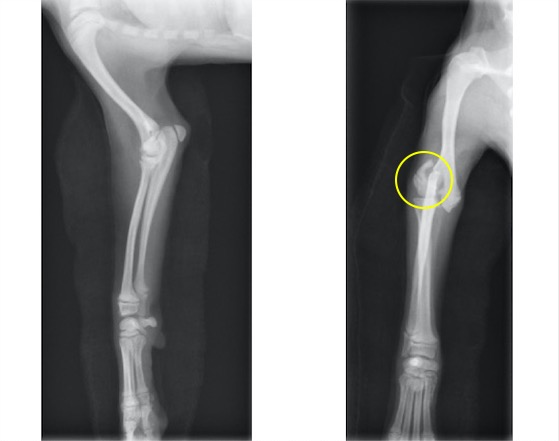

単純X線検査における四肢の成長板(矢印が成長板です)

柴犬 雌 6ヵ月齢

自転車の後部座席より落下、右前肢の挙上を主訴に来院。

触診上、手根部の腫脹と圧痛が認められました。

単純X線画像検査上、側面像では大きな左右差は認められませんでしたが、背掌像にて右前肢の軟部組織の腫脹と成長板の間隙が広くなっていることから橈骨遠位成長板骨折(Salter-Haris Type1)と診断し、外科的処置を行いました。

初心時のX線画像検査初見 赤矢印:軟部組織の主張、黄矢印:橈骨遠位成長板(左前肢と比較すると、成長板の隙間が広くなっております)